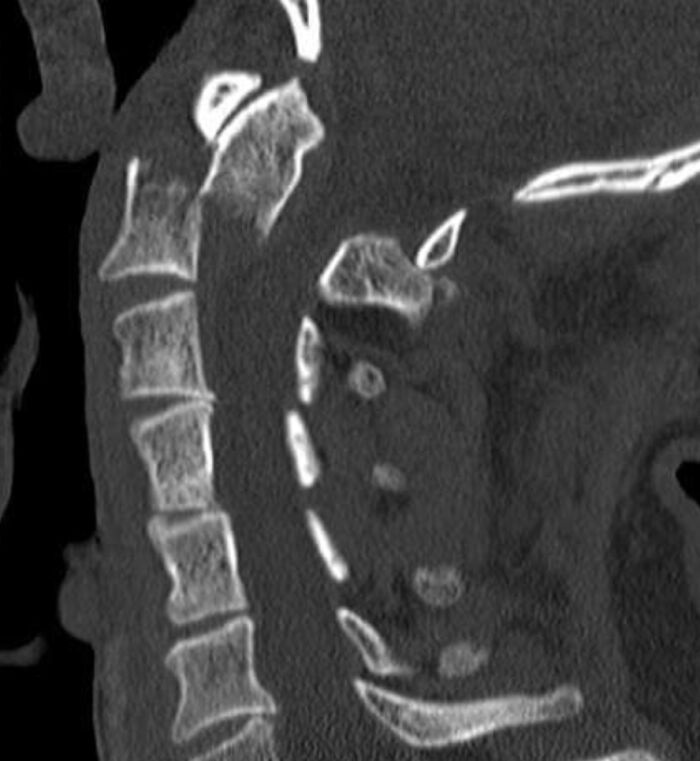

Not a doctor, but a 3rd year med student. During my neurosurgery clerkship this year, a patient came into the ER after being hit by a car. While looking at the head and neck CT, one of the residents said "holy s**t y'all come look at this." The patient's dens of his C2 vertebra (axis) had jumped under and to the front of his C1 vertebra (atlas). Basically the guy was internally decapitated and any sudden neck movement could k**l him. Weird part is he had zero neurological deficits. No paralysis or loss of function. He should have been dead but lived with no lasting effects of the injury.

Not a doctor, but my dad was in a major dirtbiking accident a couple years ago, he broke his c2 and pretty much decapitated himself internally. His ER doctor said that the only break he's seen like it was on people in the morgue. No one could understand how he was alive. Anyways, by a complete miracle, he did live, and after months in a hospital, he's breathing, eating on his own, walking, and even driving and dirtbiking again. Completely a miracle, he's numb from the head down, but it is still incredible. His doctors told their friend doctors who told their doctor friends because of how crazy it all was.